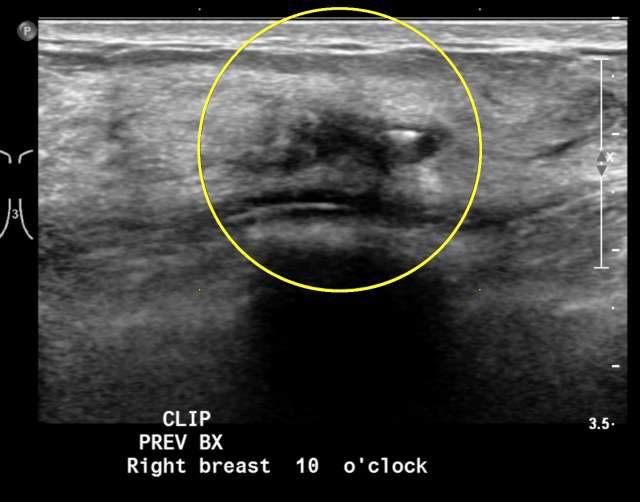

Imaging Appearance

The imaging appearance of FEA, as with other columnar cell changes, is non-specific. The most common presentation is grouped, amorphous calcifications on mammography.1,2 Likewise, the ultrasound appearance is non-specific, but it most often presents as irregular mass.2 The MRI appearance of FEA is not well-established and is also likely non-specific.1,2